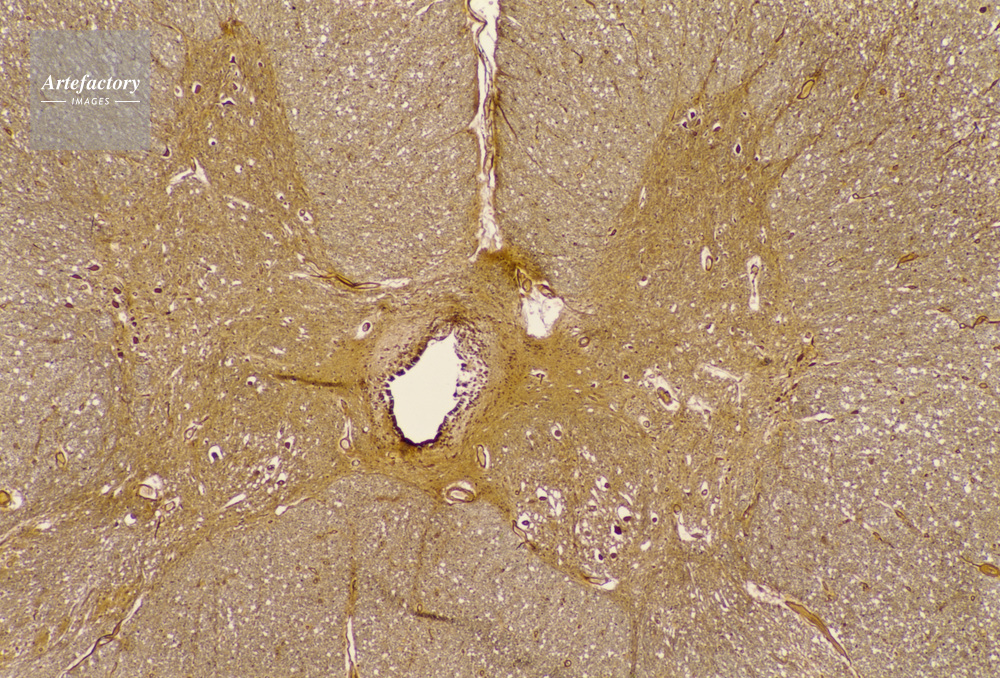

| キャプション | 脊髄,人間,20倍 | 制限事項 | ||

| ソース | ピクセル数 | 5562px × 3769px | ||